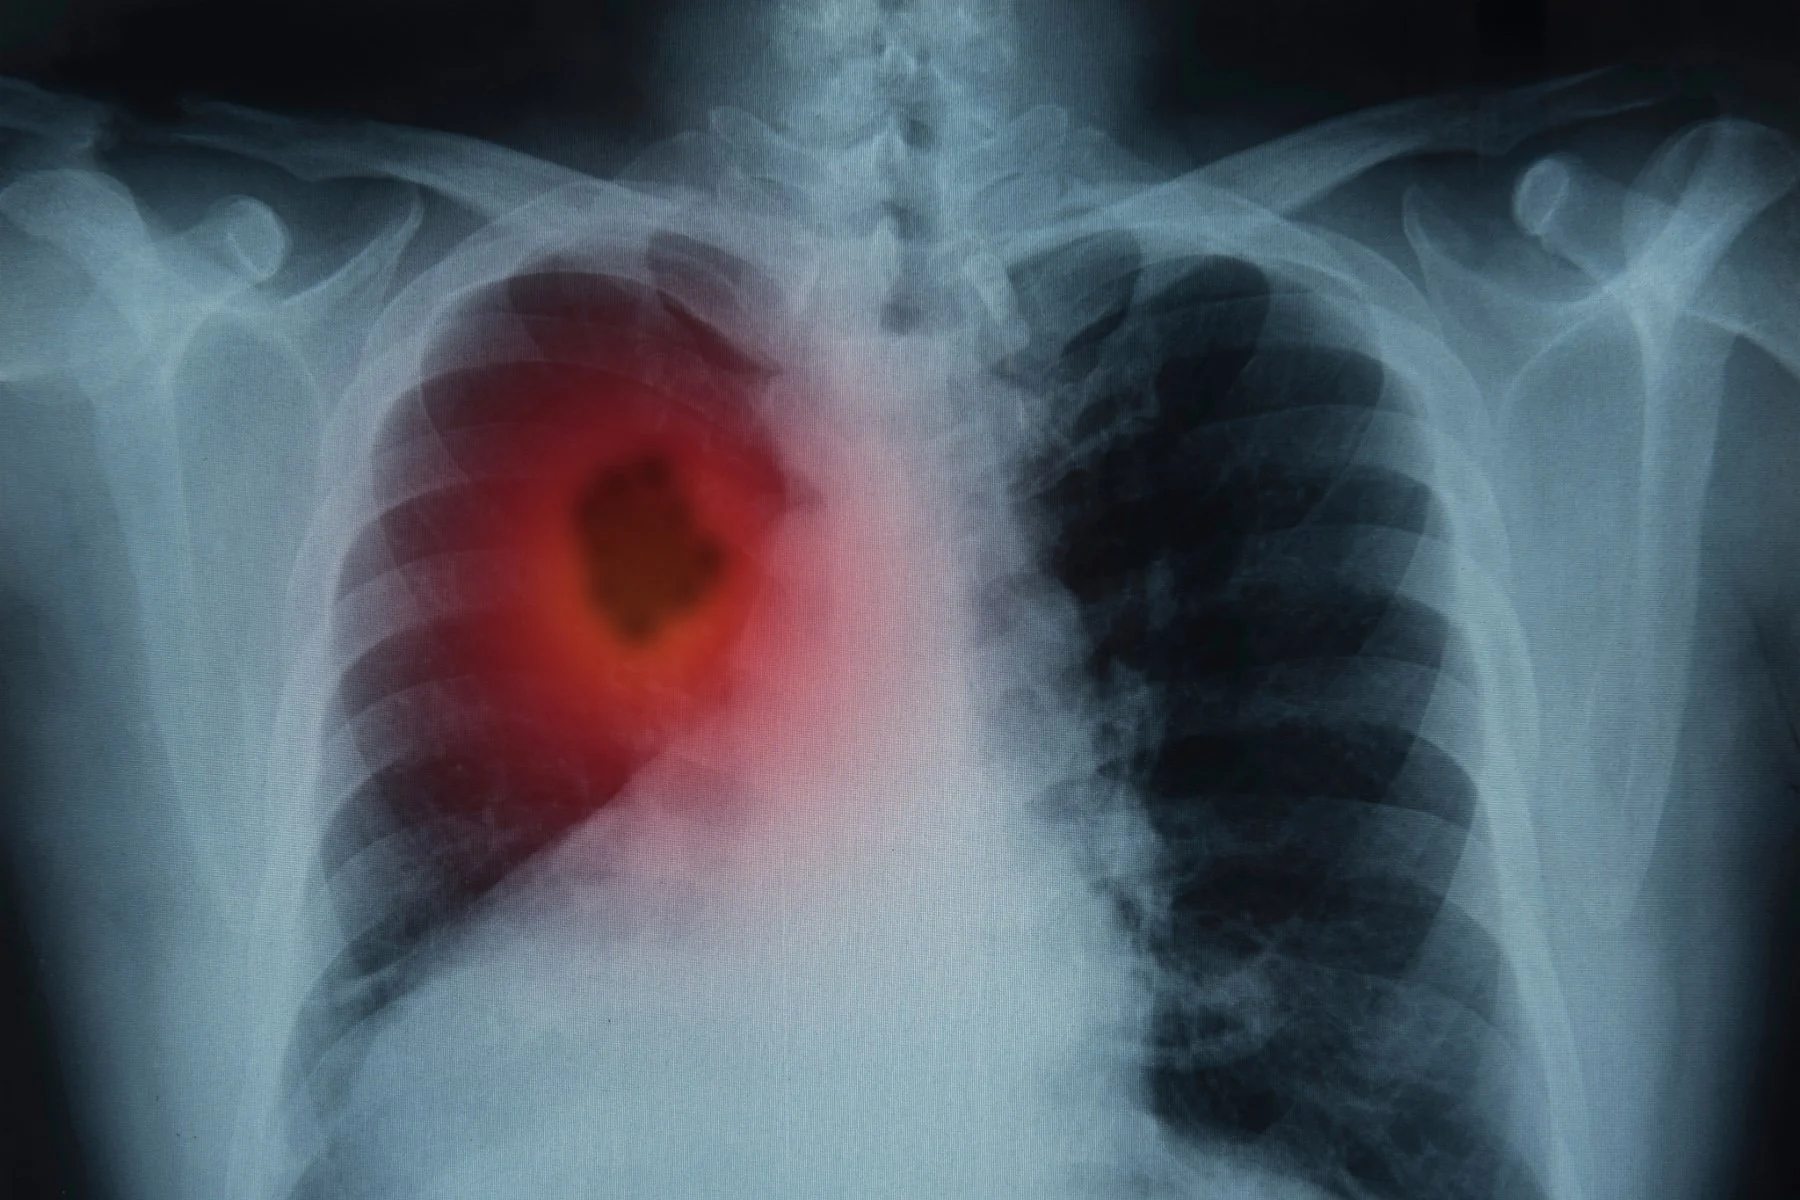

At Cizzle Bio, we’re on a mission to revolutionize early lung cancer detection with our groundbreaking CIZ1B biomarker test. This minimally invasive, highly accurate blood test is designed to detect lung cancer at its earliest stages—before symptoms appear and when treatment is most effective. The power of early detection gives patients a crucial advantage in their fight against the disease.

Why Early Detection Matters

Every day, nearly 5,000 lives are lost to lung cancer, with most cases diagnosed at late stages when treatment options are limited. Yet, early detection can make all the difference in giving patients better outcomes. 1

Our CIZ1B biomarker test offers a powerful alternative to traditional early detection methods such as low-dose CT (LDCT) scans. Unlike LDCT, which can lead to false positives and costly follow-ups, our biomarker-based blood test is accurate, accessible, and minimally invasive. With 95% sensitivity for Stage I detection4 and Negative Predictive Value (NPV) at 96%4, the CIZ1B test provides quick, reliable results that support more informed clinical decision-making.